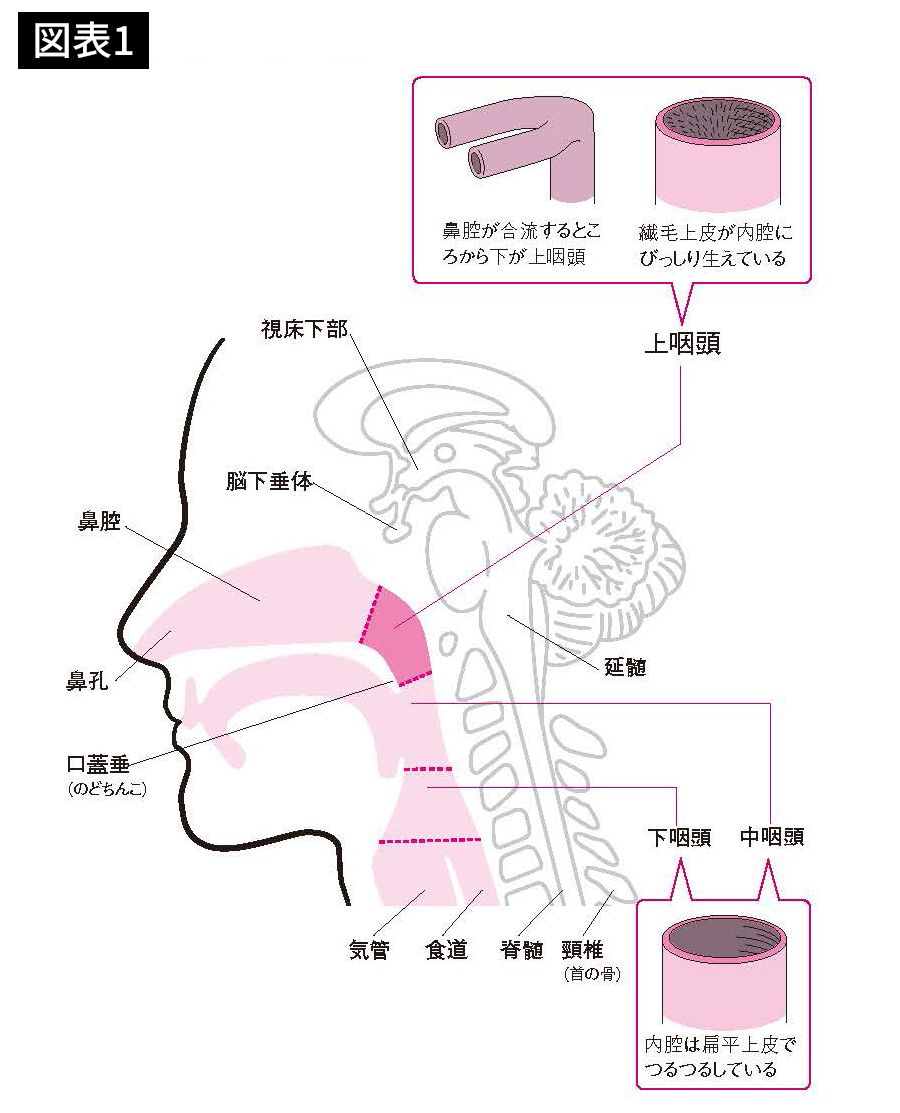

口から喉にかけての部位の名称(鼻腔・口腔・上咽頭・中咽頭・下咽頭・声帯)

「新型コロナにも有効」1日2回の"痛くない鼻うがい"で感染リスクは低下する うがいが必要なのは口ではなく鼻